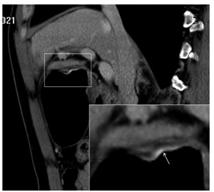

胃食管结合部癌发病率一直呈上升趋势,胃窦部癌发病率呈下降趋势。但总体而言,发病率排名第一的好发部位还是在胃窦部。而EGC 好发于胃角,此位置肿瘤往往平行于轴位图像,可能受部分容积效应影响无法在轴位清晰显示,结合冠状和矢状位后可以较好地解决这一问题(图2、3)。